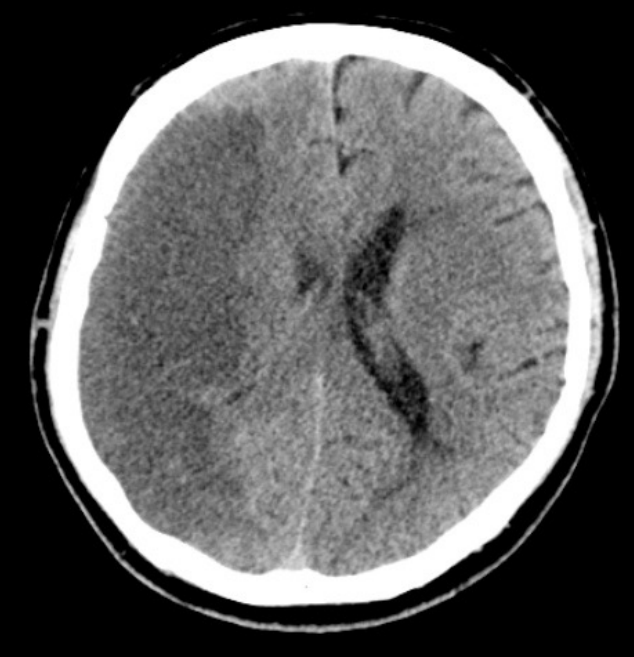

Name the pathology

MCA infarct (necrosis)